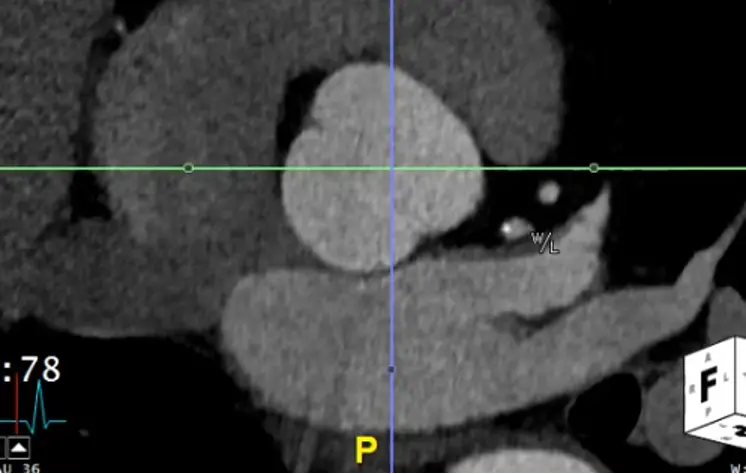

Measure at Sinotubular Junction

- Drag the lines to the sinotubular junction, i.e. where the sinuses and the tubule combine

- In the axial view, the âtrue short axisâ should be pretty close to appearing like a circle.

- đ Hit

Xto get the cross-hairs off.

- Hit

Alt+Dto automagically measure - Right click and Capture to stash the image and measurement